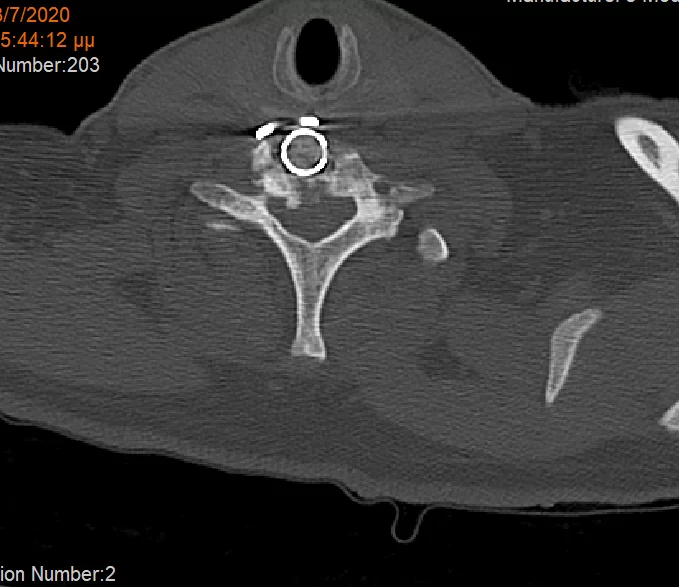

Αρχικά έγινε οπίσθια σπονδυλοδεσία προκειμένω να στηριχθεί ο αυχένας της ασθενούς και να μειωθούν τα άλγη τα οποία οφείλονταν στην “αστάθεια” της αυχενικής μοίρας. Παράλληλα, διενεργήσαμε και οπίσθια τρηματεκτομή ώστε να εξασφαλίσουμε την απελευθέρωση της δεξιάς Α7 ρίζας, η οποία δημιουργούσε πόνο στην ασθενή. Όπως φαίνεται στη μετεγχειρητική αξονική τομογραφία, οι βίδες στους αυχένες του Α4 σπονδύλου τοποθετήθηκαν με ακρίβεια χιλιοστού. Σ’ αυτό, σημαντική ήταν η βοήθεια του διεγχειρητικού νευροπλοηγού σπονδυλικής στήλης με το πιο σύγχρονο σύστημα απεικόνισης (Ο-arm II)